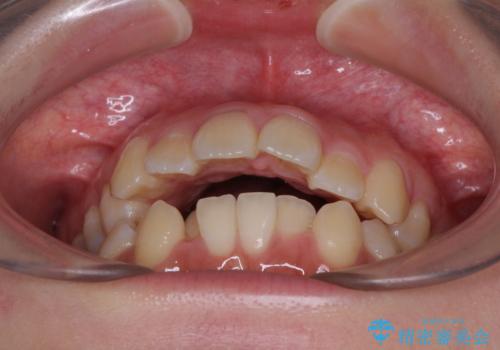

- 下の前歯のデコボコと、口元の突出感を改善したいと来院された患者様です。

突出感の強い上顎前歯をしっかりと後方移動させるため、上顎の裏側の補助装置(リンガルアーチ)とアンカースクリューを併用しています。

上下左右の第一小臼歯を抜歯して、目立ちにくいワイヤー装置で矯正を行いました。